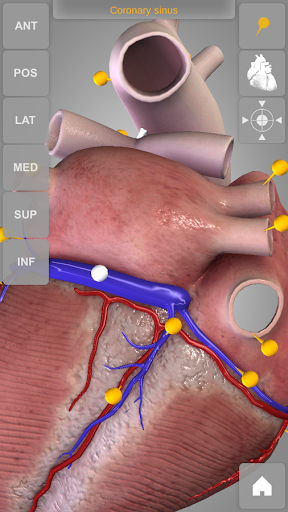

Heart 3D Atlas of Anatomy allows you to rotate a highly realistic 3D heart model as it was in your hands.

The human heart anatomical 3D model is revolvable in any direction giving a 360° view of the object.

User can choose external view or section view. Moreover, the names of specific anatomical areas can be shown touching the related pins (available in the full version only).

Heart app is part of 3D Atlas of Anatomy collection, a human anatomy reference atlas for tablet and smartphone devices. The 3D medical models in these apps are similar to classic real plastic models but with the great benefits to be always available on your portable devices when you need them and occupy no physical space.

These apps can be of great help for students of medicine or to anyone who needs to study human anatomy shape in detail and from any angle. Immediacy and simplicity together with high quality are distinctive features of the app.